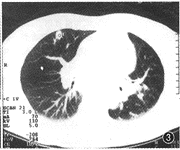

1个月后复查胸片见左肺病灶部分吸收。4个月后复查胸片见左肺病灶吸收,肺门扩大,纵隔增宽。胸部CT扫描:纵隔淋巴结肿大伴中心坏死。两肺见多发性小结节影,左下肺呈间质性改变(图2,3)。纤维支气管镜见左右主支气管呈外压性改变。活检病理报告:肉芽肿性炎症。患者再次入院时除低热、咳嗽外还诉左上腹不适。B超检查示脾肿大,脾内见多发异常回声灶。腹部CT平扫:肝未见异常,脾脏明显肿大,密度不匀,其中见多发性大小不一、边缘模糊的低密度灶(图4)。先后作2次脾穿刺活检。病理报告:肉芽肿性炎症,何杰金病不能排除。此时开始不规则服用强的松治疗,但发热一直不退,患者自动出院。

图2,3 发病4个月肺CT检查示纵隔淋巴结肿大、并坏死形成,双肺结节性病变伴左下肺间质改变